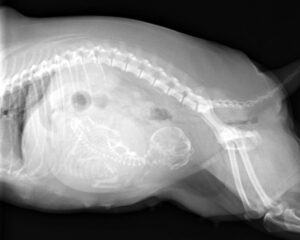

ポメラニアンちゃんの帝王切開でした。無事元気に生まれました。よかったね。